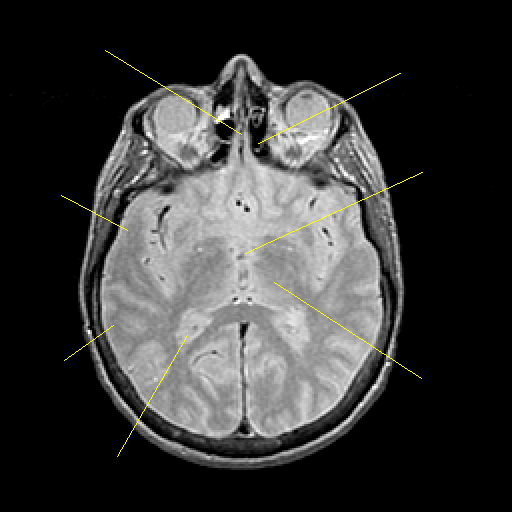

Proton density-weighted structural MR: Slice 26

Slice 26

Pointers

Labeled